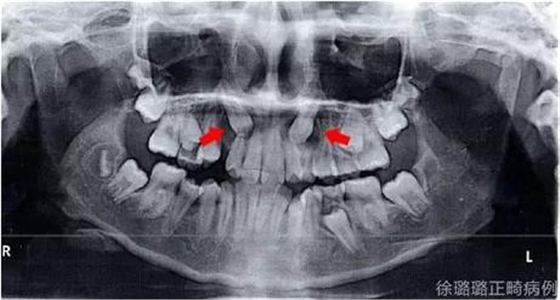

影像學(xué)檢查

360截圖20170120124727674.jpg

X 線檢查:替牙列,上頜雙側(cè)尖牙埋伏阻生(含牙囊腫),四顆第三恒磨牙牙胚存在。